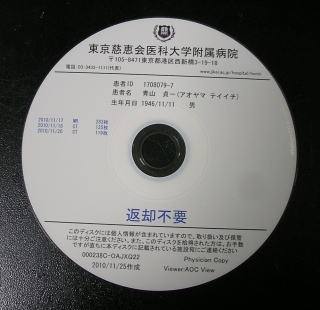

そして翌日の11月19日午後から夜に及ぶ手術では、妻が個室(病室)に待機し、万一インフォームドコンセントの内容からはずれて麻酔、手術などをする場合、すぐに執刀医から妻に連絡が行くとされた。 手術では、当初通りに行われたこともあり、待機する妻への連絡は終了時までなかった。 ◆手術の具体的内容 C1が第一頸椎、C2が第二頸椎であり、上の図が側面図、下の図が組の後ろから見た側面図である。スクリュー4本、ロッド2本は素材がチタン合金であい、櫓を組んで第一、第二頸椎を腰から取った自分の骨を挟んで固定する。  主治医がInformed Consentで示した青山貞一手術の概念図(1) 慈恵医科大付属病院脳神経外科 2010.11.18 下は青山が上図を元にのちに作成したもの。ただし、下図は第二頸椎骨折、陥没後ではなく、健康な頸椎上にチタンのスクリューやロッドを書き加えている。さらに3次元で立体的に可視化しないとその構造は理解されにくい。  青山貞一による手術の概念図 下は使用するチタンスクリューのイメージである。   出典:http://www.sophiatech.co.jp/implans/screw_image/screw_image.html 手術ではたとえば以下のようにして使うことになる。ただし、以下はイメージ図。   それぞれの位置 背面図 出典:http://www.orihime.ne.jp/~one-/tekious.htm 手術の前々日、前日と2回に渡り麻酔専門医から何度も説明を受けた。麻酔の手順、心得などについても説明を受けた。 大手術は慈恵医科大学付属病院の脳神経外科、麻酔科などの専門医師5名による特別グループ構成で11月19日午後から夜にかけ行われた。 12時過ぎ、中央棟16階にある私の個室から看護師により車椅子で16階からエレベータを使って3階の手術に向かった。手術室到着後、麻酔専門医により点滴形式で全身麻酔が行われた。覚えているのはここまでである。 その後7-8時間はまったく記憶はなく夢も見ていない。 手術後すぐに、5階にある集中治療室(ICU)に移された。 ICUでは主動脈(Aライン)、静脈、末梢系はじめ各所に10本以上のチューブが体に差し込まれており、またオシッコなどの排出系もすべてチューブとなっていて身動きできなかった。入院後、一番きつかったのはこのときである。 慈恵医大病院中央棟のICUはかなりの数あり、手術を受ける患者には希望すると手術の前日までにICUを見学することができる。私は希望し前日にしっかり見学しICU側から説明も受けた。 肝腎な手術の内容は、上述のように落下転倒で折れ陥没した第二頸椎と第一頸椎の間に、腰から取った骨を挟み約2mm直径のチタン(金属)2本とそれにブリッジをかけるように固定することでした。チタンの棒は計4本使用している。 上記の手術内容についても、外来検査時から手術の前日まで、あらかじめ模型とグラフィックスをもとに主治医に何度も説明をしてもらった。 手術内容と方法には、当然のこととして代替案が多数ある。そのかかから医師と議論しながらひとつを選ぶことになった。代替案によりプラス、マイナス、リスク、費用が変わる。 また、もし手術で実際に首を開いたところ、第一案が難しい場合は第二案、第三案と次善の策についても優先順位を付けることになった。この説明と質疑にはかなりの時間が費やされた。この辺はInformed Consentの主要部分となる。 本来、第一頸椎と第二頸椎はそれぞれ独立して動くことで、人間は誰でも首が自由に回るのだが、第一と第二を固定化したので、手術によって直っても仰角、回転角ともに制限がある。リハビリなどにより健康な方の70%程度まで戻るかも知れないと言われた。 上述のように、私自身、3週間に及ぶ入院の中では、ICUから個室に移った20日が一番きつかった。翌日は一日安静にしていた。実のところ私が入院中に安静にしていたのは、この日(20日)くらいかも知れない。 19日夜から点滴が開始されていたが、20日の夕方から食事がだされた。食事と並行してブドウ糖などの点滴を行い栄養を体に送り込んだ。点滴にはブドウ糖とともに手術時の各種傷口に対応するための抗生剤が含まれる。 22日以降、手術に関連した痛みがかなり減ってきた。術後、一切の鎮痛剤を使っておらず看護師さんらはびっくりしている。痛みは人によって個人差があるようだ! ところで今回は、11日に東京都品川区にある旗の台脳神経外科に診察にでかけたときから、現在に至るまで徹底的にInformed choice and consentを心がけ、すべてに渡り主治医(脳神経外科執刀医、呼吸器主任、糖尿など生活習慣病関連の主任、麻酔主任)らからの説明を受け、その都度理解、認識した上で判断した。 たとえば呼吸機能を回復させようとすると血糖値やLDLが上昇するなど新たな問題が起こるが、それらを承知の上で何を優先するかが術前の大きなポイントとなる。これについても、私のここ数年の経験を伝えた。 医者側も驚いていたが、やはり患者や家族は医者任せ、看護師まかせではなく、主体性を持って対応することの大切さを実感している。 下は健康な人の第一頸椎(上)と第二頸椎(下)の側面図である。 第一頸椎 出典:http://video.about.com/backandneck/Cervical-Spine-Anatomy.htm 第二頸椎 出典:http://video.about.com/backandneck/Cervical-Spine-Anatomy.htm 下のレントゲン写真は術後に撮影したものである。 退院後初の検査時に主治医より提供を受けた。第一頸椎と第二頸椎の間に腰骨を挟み、チタン合金で第一頸椎(長いスクリュー)、第二頸椎(短いスクリュー)で固定している様子が3次元の立体図で良く分かる。  手術後の頸椎レントゲン写真(2010/12/13) 出典:東京慈恵会医科大学付属病院脳神経外科 以下は、CT及びMRIで見た手術個所の断層図である。退院時、希望していたCT及びMRI断層画像データをCD媒体で提供された。画像は専用ソフトだけでなくWindowsXP,7などのブラウザでも見れる。  出典:東京慈恵会医科大学付属病院脳神経外科 下はCT画像に見る第二頸椎に入れたチタンスクリュー(ネジ)。断層撮影なので部部しか見れない。  CT断層画像に見る青山貞一の手術後(2010年11月20日撮影)。 慈恵医大付属病院 下もCT画像に見る第二頸椎に入れたチタンスクリュー(ネジ)。断層撮影なので部部しか見れない。チタンスクリューは4本、チタンロッド(棒)は2本入れてある。  CT断層画像に見る青山貞一の手術後(2010年11月20日撮影)。 出典:慈恵医大付属病院脳神経外科  CT断層画像に見る青山貞一の手術後(2010年11月20日撮影)。 出典:慈恵医大付属病院脳神経外科  CT断層画像に見る青山貞一の手術後(2010年11月20日撮影)。 出典:慈恵医大付属病院脳神経外科  CT断層画像に見る青山貞一の手術後(2010年11月20日撮影)。 出典:慈恵医大付属病院脳神経外科  CT断層画像に見る青山貞一の手術後(2010年11月20日撮影)。 出典:慈恵医大付属病院脳神経外科 下は腰の骨の採取場所を示している。また手術時の切開位置を示している。首の裏を縦に12cmほど切開している。  主治医ががInformed Consentで示した青山貞一手術の概要図(2) 慈恵医科大付属病院脳神経外科 2010.11.18  頸椎を取り巻き上下に縦断する筋肉 出典:http://video.about.com/backandneck/Cervical-Spine-Anatomy.htm  頸椎と隣り合わせに上下に縦断する脊髄 出典:http://video.about.com/backandneck/Cervical-Spine-Anatomy.htm 万一動脈を切った場合は、すぐに輸血を開始するという。  頸椎と隣り合わせに上下に縦断する動脈 出典:http://video.about.com/backandneck/Cervical-Spine-Anatomy.htm 下は慈恵医大付属病院のCTで撮影した青山貞一の頸椎と隣り合わせに上下に縦断する動脈である。  CT断層画像に見る青山貞一の頸椎と隣り合わせに上下に縦断する動脈(撮影2010年11月17日)。 出典:慈恵医大付属病院脳神経外科 英国医学会で頸椎手術に関連し想定しているリスク(合併症を含む)を以下に示す。すなわち外科手術により物理的に幹部を固定化したとしても、将来、以下のようなリスクがないわけではないようだ。  出典:http://video.about.com/backandneck/Complications-of-Spinal-Surger.htm ◆全身麻酔による大手術 入院から一週間後の11月19日午後、全身麻酔後に大手術をすることになった。慈恵医科大学付属病院の中央棟3階にある手術室で手術を受ける。 手術の数日前から麻酔の専門医2名から説明を受ける。また看護師から手術当日の実務手順について資料をもとに説明を受ける。 お昼に病室がある16階から専用エレベータで手術室がある3階に直行し、その後、麻酔との対話の中で点滴により全身麻酔がおこなわれ、5名のチームによる手術が開始された。 慈恵医大脳神経外科の手術では全国でここだけ、手術中にCT断層撮影が可能とのことである。 午後8時過ぎ手術は終了し、5階の集中治療室(ICU)に移された。麻酔が切れた後、妻や池田さんと会話を交わした。大手術は大成功であった! 現在の麻酔技術の進歩はすさまじく、5分単位で全身麻酔をオンオフできるという。医師は麻酔技術は日進月歩で進歩しており、すばらしく切れがよいと言っていた。  慈恵医大病院中央棟3階にある手術室のイメージ 3階、4階が手術室。5階が集中治療室(ICU)、6階より上が病棟 出典:慈恵医大病院公式Web  集中治療室(ICU)の一部(イメージ) 出典:慈恵医大病院公式Web このように11月19日午後から夜に行われた手術では、当初予定の内容を関連する神経系、動脈系などに損傷を与えることなく実施できた。 ★手術成功のお知らせ(池田こみち) 術後の痛みだが、鎮痛剤を注射してもらうほどの耐えられない痛みは退院までなく、当初からあった後頭(こうとう)神経痛も次第に弱くなってきた。それ以外の痛みとしては、寝る角度により腰から骨を採った場所がちくりと痛むことがル程度である。 以下は青山貞一の手術を担当してくれた大橋医師のプロフィールです。